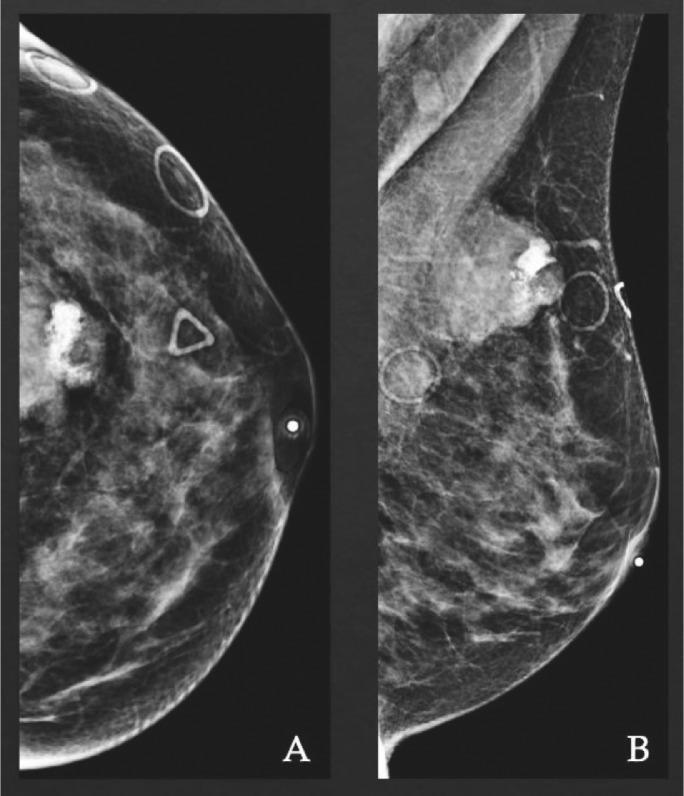

Metaplastic breast carcinoma is an uncommon malignant tumor with various pathologic subtypes. Diagnosis is often challenging due to the wide spectrum of clinical and imaging presentations. Here, we present the case of a very rare subtype of metaplastic breast carcinoma-a mixed-type metaplastic breast cancer with osseous differentiation in a 55-year-old female patient. The clinical presentation, imaging-pathology diagnosis, and treatment options are reviewed. Knowing this rarely reported but aggressive breast cancer is very important for clinicians to establish a timely diagnosis for effective management.

化生性乳腺癌是一种具有多种病理亚型的罕见恶性肿瘤。由于临床和影像学表现范围广泛,诊断往往具有挑战性。在此,我们报告一例非常罕见的化生性乳腺癌亚型——一名55岁女性患者的伴有骨分化的混合型化生性乳腺癌。本文对其临床表现、影像-病理诊断及治疗选择进行了综述。了解这种罕见但侵袭性强的乳腺癌对于临床医生及时做出诊断以进行有效管理非常重要。